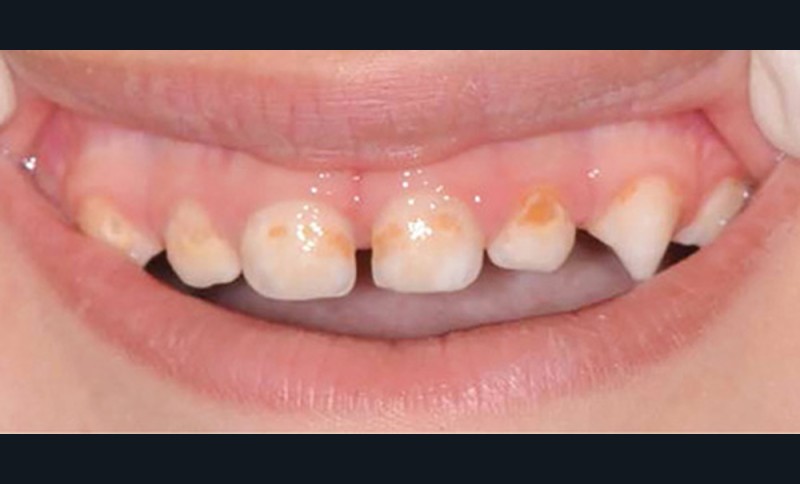

Dès l’atteinte d’une face de l’émail de la couronne dentaire, un traitement doit être proposé. Les traitements généralement conservateurs seront gradués selon la sévérité et l’activité de la lésion carieuse (fig. 1).

- L’évolution de la maladie carieuse : cette pathologie bactérienne, multifactorielle, se transmet très vite d’une dent à une autre dans la cavité orale de l’enfant. Ainsi, avant l’âge de 6 ans, la carie précoce de l’enfant (CPE) peut atteindre un stade sévère et ne plus permettre à l’enfant de mastiquer sans douleur (fig. 2).